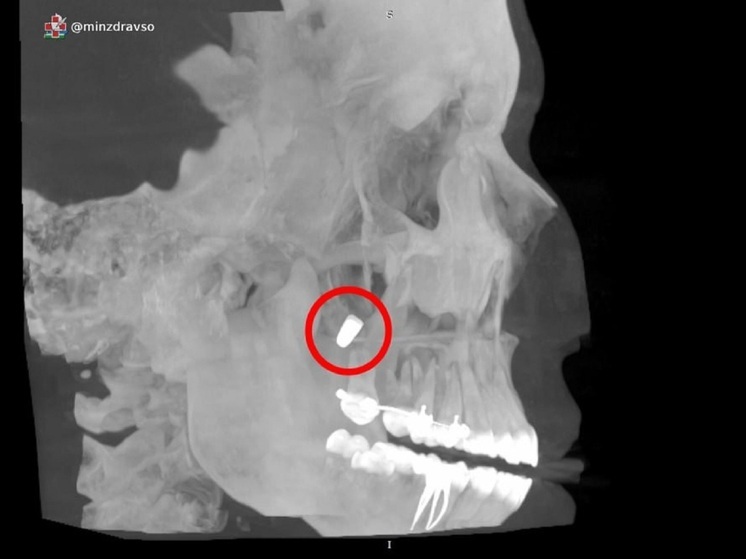

Специалисты Центра «Бонум» при поддержке Свердловского Минздрава провели уникальную операцию в Екатеринбурге. Врачи эндоскопически извлекли металлический зубной имплант, который сместился в гайморову пазуху пациентки, вызвав осложнения.

По данным пресс-службы ведомства, проблема возникла после неудачной установки конструкции в одной из стоматологических клиник. Во время процедуры врач случайно протолкнул имплант в верхнечелюстную пазуху, что привело к миграции объекта в носовую область.

Женщина испытывала периодическую боль, заложенность носа и дискомфорт. Как пояснили эксперты, без своевременного вмешательства инородное тело спровоцировало бы воспаление, усиление боли и риск кровотечений.

Медики выбрали щадящую методику: через носовую полость без разрезов в ротовой области. Инновационный подход сократил реабилитацию и сохранил анатомию пазух. Сейчас пациентка полностью восстановилась и готовится к новому этапу имплантации после наращивания костной ткани.